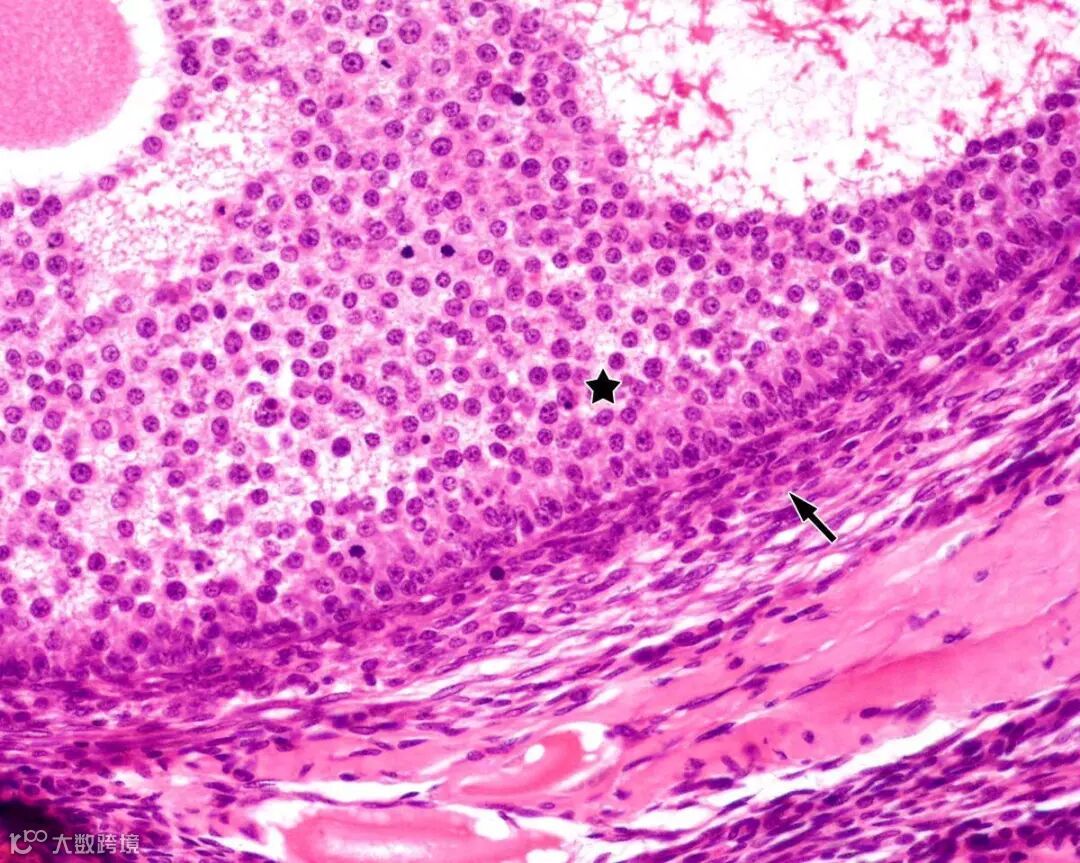

△显微镜下的卵巢颗粒细胞

颗粒细胞是一种卵巢合成和分泌抑制素、雌激素的主要功能细胞,在女性卵泡的生长、发育和成熟,黄体生成等方面发挥着重要作用。